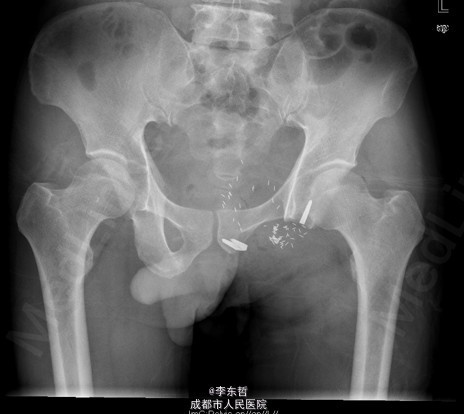

查体:臀部、会阴部、下腹部未触及包块,左下肢前内侧皮肤感觉较对侧减弱,双侧膝反射、跟腱反射正常引出,肛周皮肤感觉减退,直肠指检可触及质韧包块,活动度较差。双下肢肌力5级,双下肢各关节活动度可。 辅查:外院增强CT示:盆腔左侧壁见团块状软组织密度影,密度不均,其内见多发斑块高密度影,病灶大小约9.4*7.6cm,增强后强化不明确。我院X片示:左侧闭孔及耻骨区见不均匀高密度影,大小约6.2*6.7cm。我院MRI示:盆腔左份见长T1长T2肿块影,大小约10.3*7.7*10.5cm,向前推挤膀胱,向右推挤前列腺。我院骨扫描显示:耻骨联合及左侧耻骨支核素浓集。